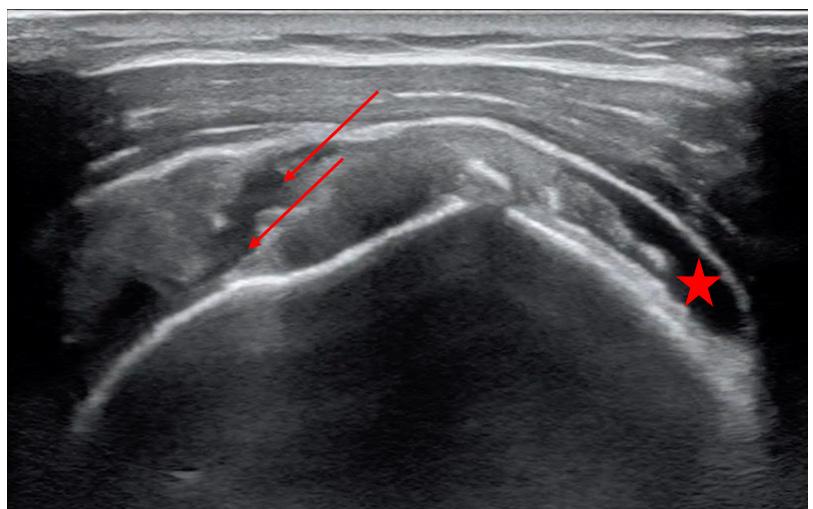

Figure. Combined feedback from first-year emergency medicine residents on five separate community site visits they made on Community Engagement Day 2021 and 2023. ED, emergency department.

affected by SDoH.